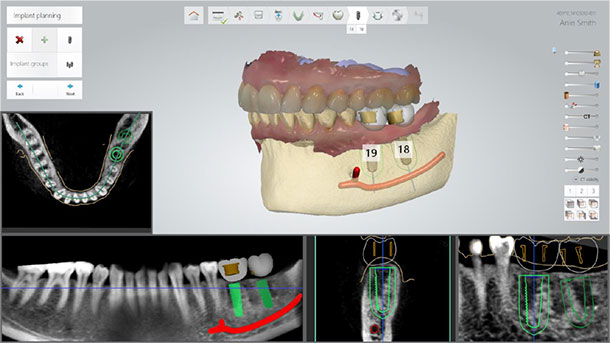

Practice intraoral scanning and digital implant planning to build confidence in implementing efficient, modern workflows.

Immediate implant placement offers significant clinical and operational advantages for both specialists and general dentists—especially when paired with smart shape healing abutments that support efficient healing and streamlined workflows. This course provides clinicians with the skills and knowledge to confidently plan, place, and restore immediate implants using a fully digital approach from assessment through final prosthetic delivery. Participants will explore case selection criteria, risk factors, and complication prevention strategies while gaining insight into the biological benefits of smart shape healing abutments. The program features a blend of lecture, workflow analysis, hands-on intraoral scanning, and 2–3 live surgeries demonstrating implant techniques across various clinical scenarios. By the end of the course, attendees will be equipped to integrate immediate implant placement into their practice with confidence—enhancing patient outcomes, clinical efficiency, and treatment success through modern digital protocols.

● Identify ideal candidates for immediate implant placement using clinical and radiographic criteria ● Master digital workflows from assessment to final restoration with smart shape healing abutments ● Observe live surgeries showcasing immediate implant techniques in various anatomical sites ● Learn to prevent complications and manage risks through evidence-based protocols ● Practice intraoral scanning and digital planning in hands-on, guided sessions

Gain the confidence to place immediate implants with precision using smart shape healing abutments and digital workflows. This immersive course offers the live training and hands-on experience you need to deliver efficient, predictable results and elevate patient care.